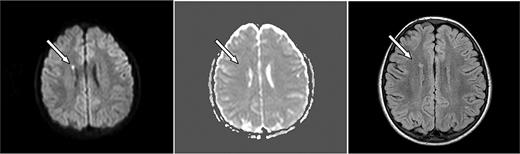

ASCIE were identified by DWI in 4 (18.2%) of 22 children with SCD and 2 (6.7%) of 30 without SCD (P = .382, Table 1). All had areas of restricted diffusion on DWI with corresponding areas of decreased signal on ADC map. There were corresponding abnormalities on the initial FLAIR images in 4 of 6. DWI lesions were subcortical or in the deep white matter (Figures 1–2). One patient had deep white matter DWI lesions and a lesion in the splenium of the corpus callosum without history of seizure. Two of the 6 patients had multiple DWI lesions, 4 had solitary lesions.

Axial MRI images of case 4. A 6-year-old boy with SCD and acute chest syndrome with hgb = 4.1 g/dL showing (left, arrow) an area of restricted diffusion on DWI images with an ADC correlate (middle). Follow-up FLAIR MRI 4 months later (right) shows a lesion corresponding to the affected area on the DWI.

Follow-up MRI studies (Figures 1–2) were obtained 2.5 to 7 months later for other clinical indications for 4 of 6 of the patients with ASCIE; 3 had lesions on FLAIR images consistent with SCI in locations corresponding to the ASCIE on the initial study MRI (Table 1) and thus meet the definition of acute SCI. All 3 had SCD. Notably, the patient without a corresponding lesion on follow-up imaging also had no FLAIR correlate on the initial study MRI. This patient did not have SCD. We believe this to be a transient, reversible ASCIE.7 Magnetic resonance angiography (MRA) was not part of our study protocol but was obtained for the clinically indicated follow-up studies for 4 of 6 of the patients with ACSIE and was normal in 3, with 1 patient demonstrating subtle vascular irregularities in the internal carotid artery and middle cerebral artery ipsilateral to the ASCIE (Table 1).